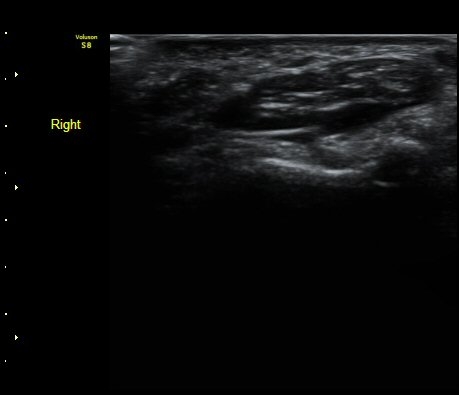

ÃÊÀ½ÆÄ °Ë»ç

¼ÒÁö±¸ ³»Ãø¿¡ ȾÀ¸·Î ŽÃËÀÚ¸¦ ´ë¾î °¥°í¸®»À °¥°í¸® ³»Ãø¸é ÇÇÁú°ñÀ» °üÂûÇÏ´Ï(¾Æ·¡ ±×¸²)

°¥°í¸® ÇÇÁú°ñ ¿¬¼Ó¼º ¼Ò½Ç(loss of cortical continuity of hook of hamate)ÀÌ °üÂûµÈ´Ù(±×¸² 1, 2).

ÇÇÁú°ñ ¿¬¼Ó¼º ¼Ò½ÇÀº °ÇÃø°ú ºñ±³ÇØ¸é ´õ¿í ¶Ñ·ÈÇÏ´Ù(±×¸² 3, 4).

ÀÌ °ñÀýÀÌ ÀǽɵǴ °æ¿ì ÃÊÀ½ÆÄ°Ë»ç¸¦ ½ÃÇàÇÏ¸é ¾ÆÁÖ °£´ÜÇÏ°Ô È®ÁøÀÌ °¡´ÉÇÏ´Ù.